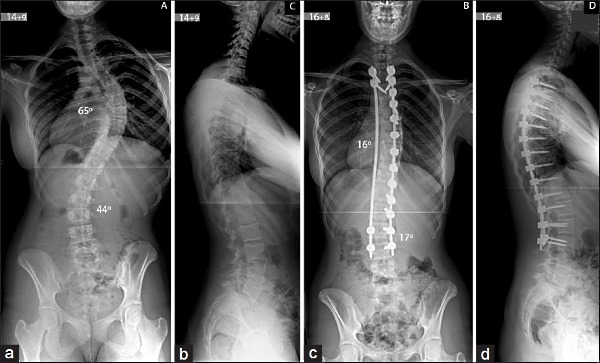

Так выглядит позвоночник до и после операции по коррекции сколиоза.